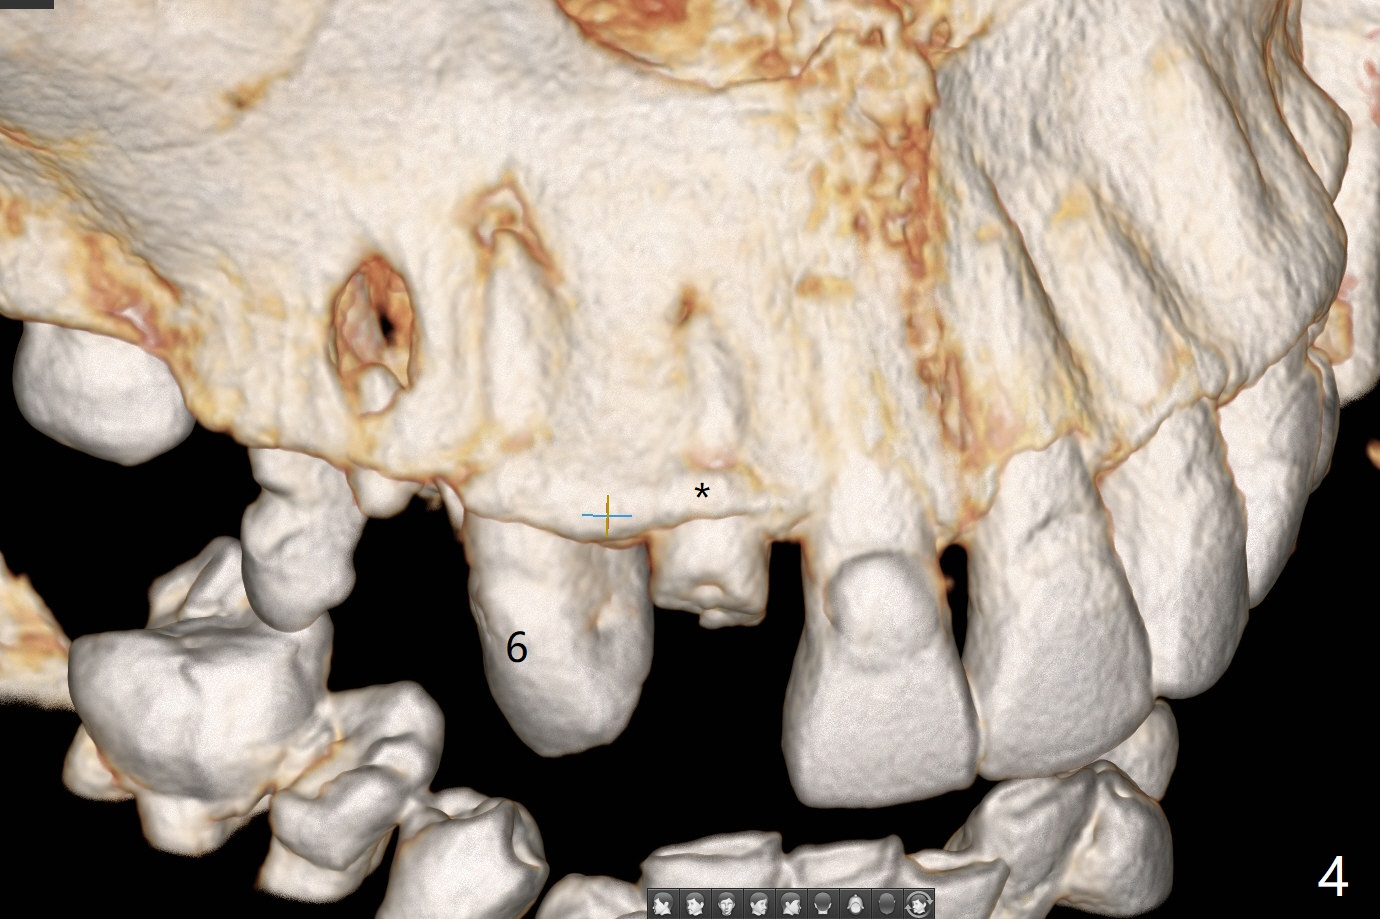

A 79-year-old man, who fractured the tooth #7, has several Class V defects (Fig.1). He seems to be a bruxer. Pay attention to occlusion and determine whether he has anterior deep bite. The neighboring tooth, #6, has apical lesion (Fig.2 <). Root canal therapy has been finished prior to implant placement (Fig.3). Prepare Tatum 1-piece implant in case the trajectory is off. If the crown height is more than 10 mm, prepare IS system. Otherwise use DIO one. If the root turns out to be difficult to extract, be ready for socket shield. Preop CT shows minimal apical perforation at #7 (Fig.4 (3-D image)). The buccal plate is thin (Fig.5 (coronal section) between arrowheads (acute infection may increase the perforation quickly)), while the crest is thick (*).